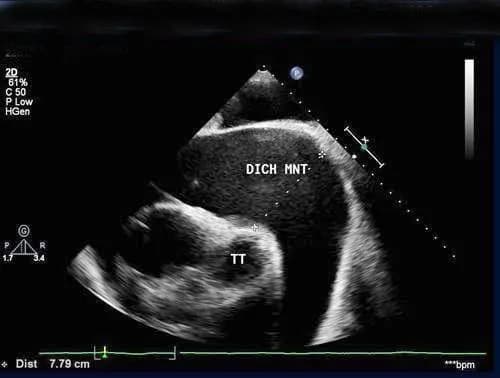

- Tràn dịch màng ngoài tim: * Siêu âm 2D: Phát hiện dịch tích tụ trong khoang màng ngoài tim, đánh giá số lượng và vị trí của dịch.* Phình tim và Giả phình: * Phình tim: Vùng thành tim bị giãn ra và mỏng đi. * Giả phình: Một vết rách trên thành tim được bao bọc bởi cục máu đông và màng ngoài tim. * Siêu âm 2D và Doppler: Xác định vị trí, kích thước, và đặc điểm của phình tim và giả phình.* Huyết khối trong buồng tim: * Siêu âm 2D: Phát hiện các khối máu đông trong buồng tim.* Thủng vách liên thất: * Siêu âm 2D: Có thể thấy lỗ thông trên vách liên thất. * Siêu âm Doppler màu: Phát hiện dòng máu chảy qua lỗ thông.* Hở van hai lá: * Siêu âm Doppler màu: Đánh giá mức độ hở van hai lá. * Siêu âm Doppler liên tục: Đo vận tốc dòng máu hở van.